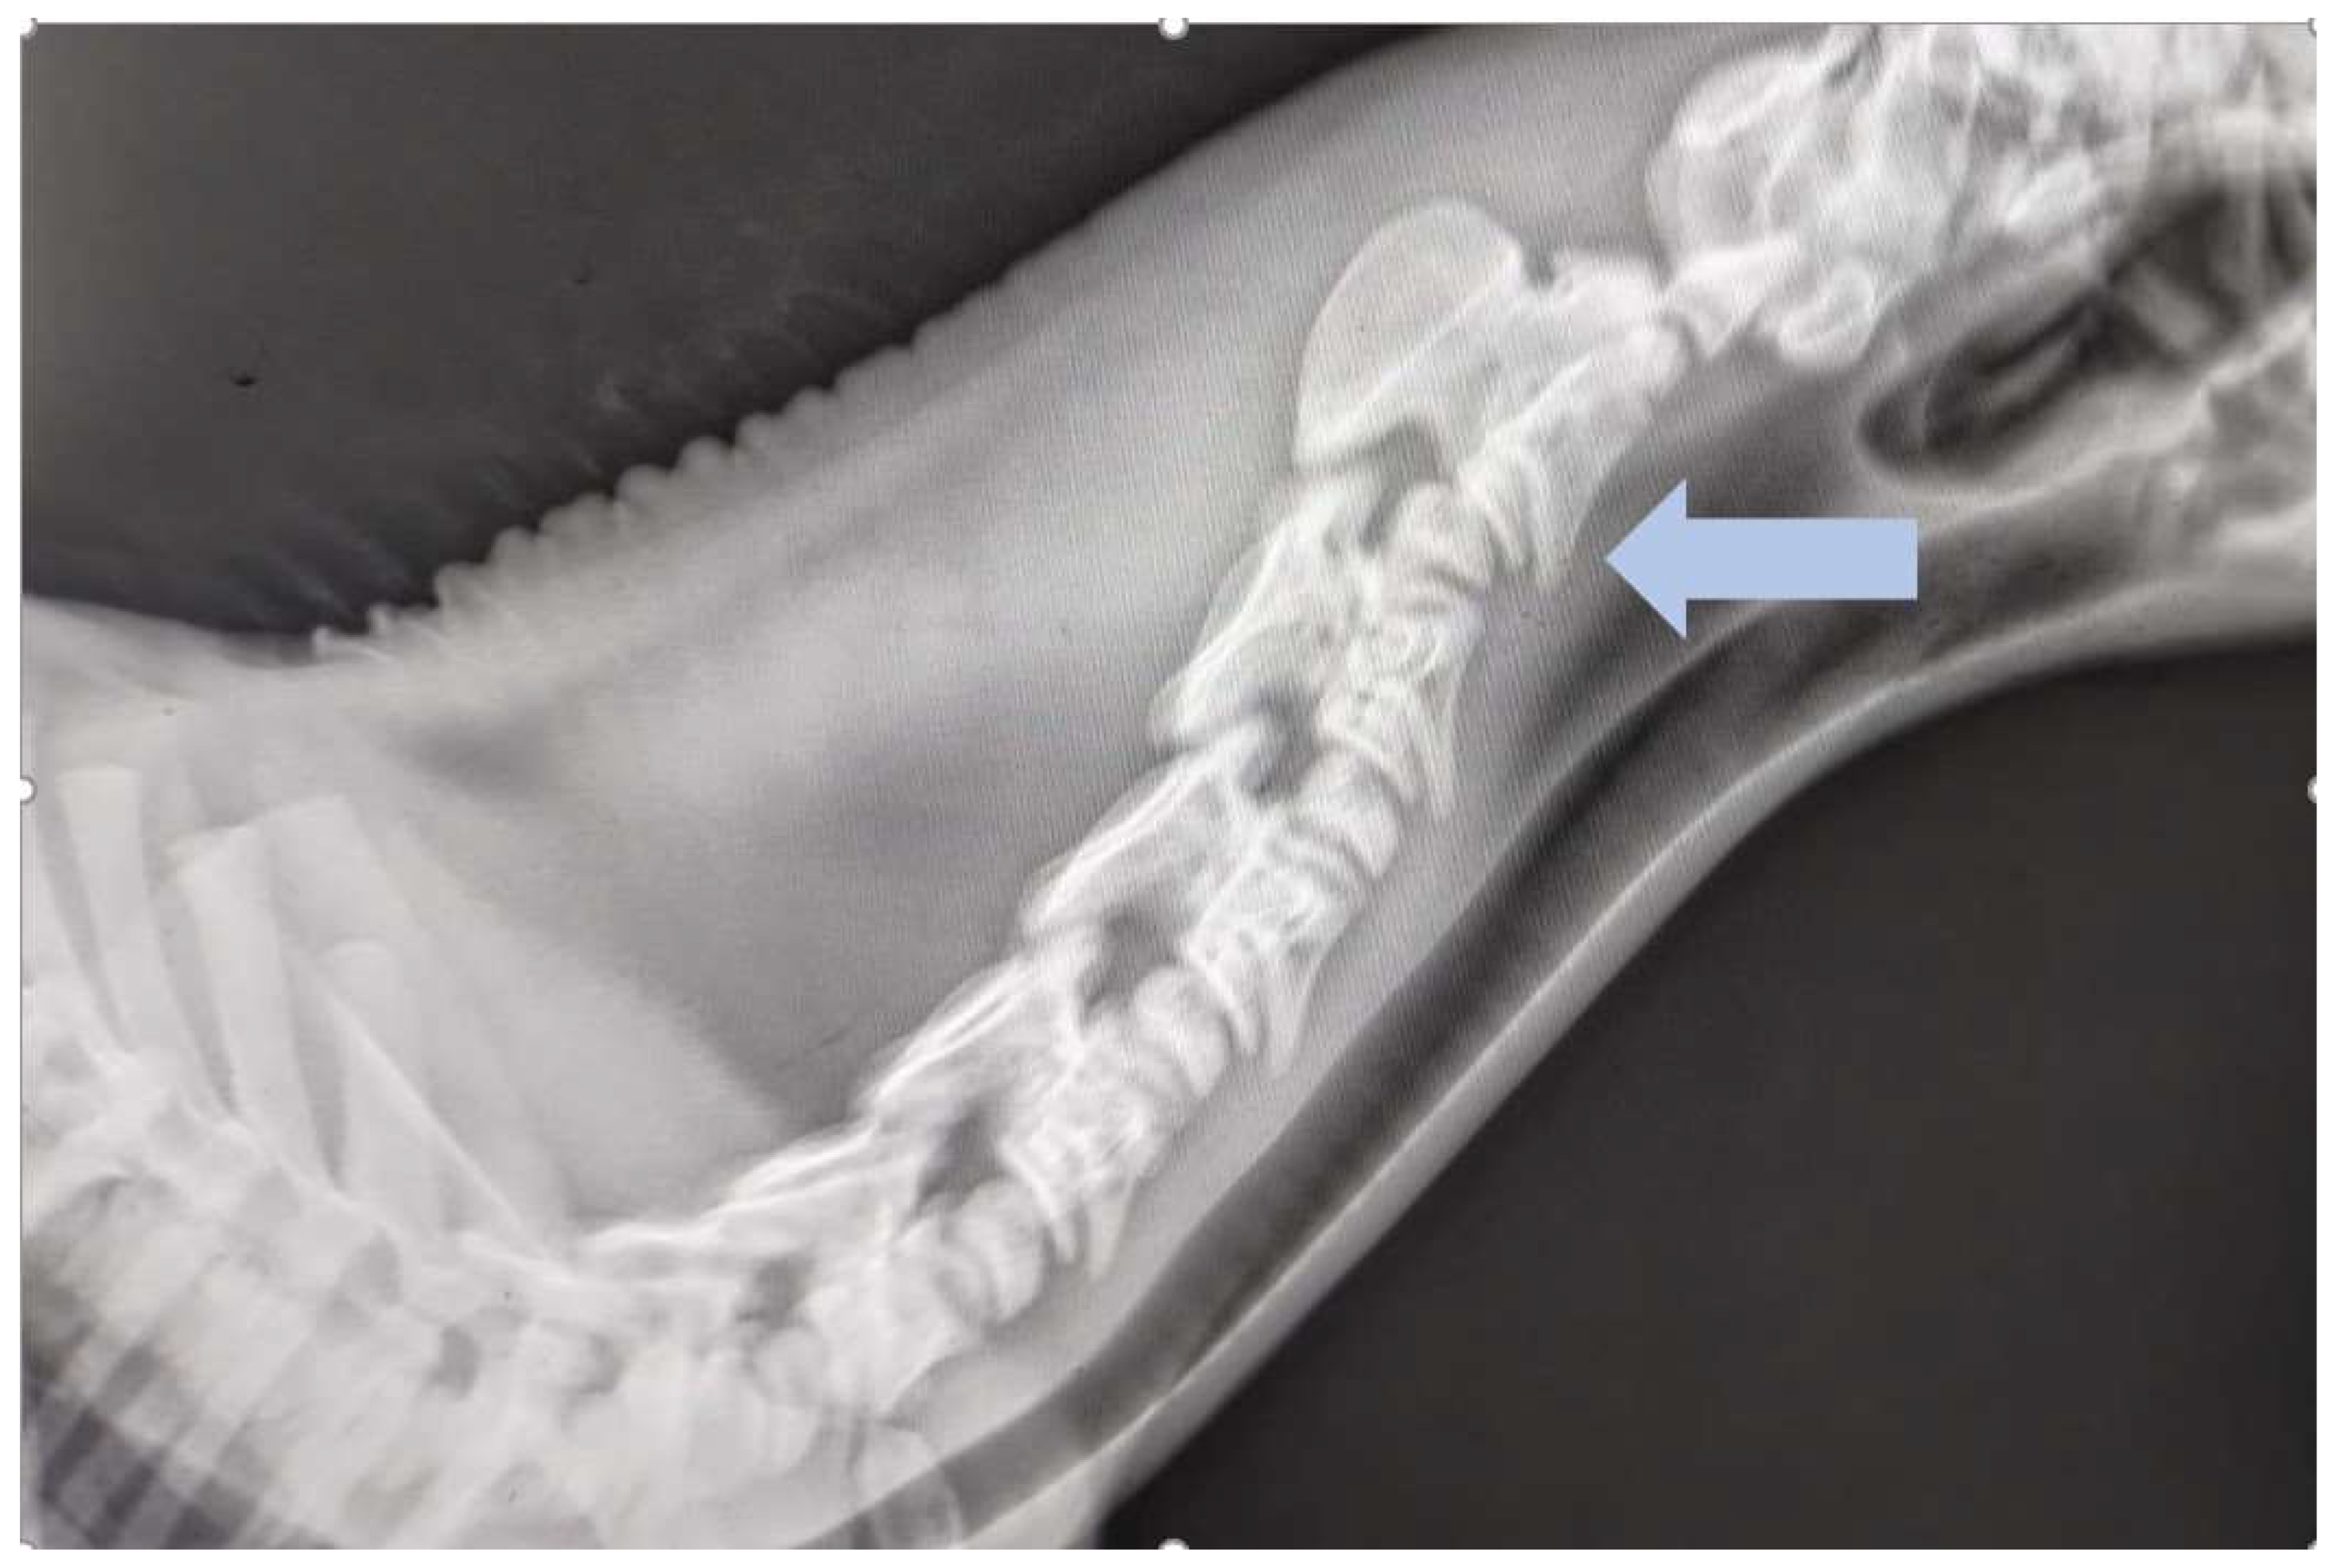

Case Presentation